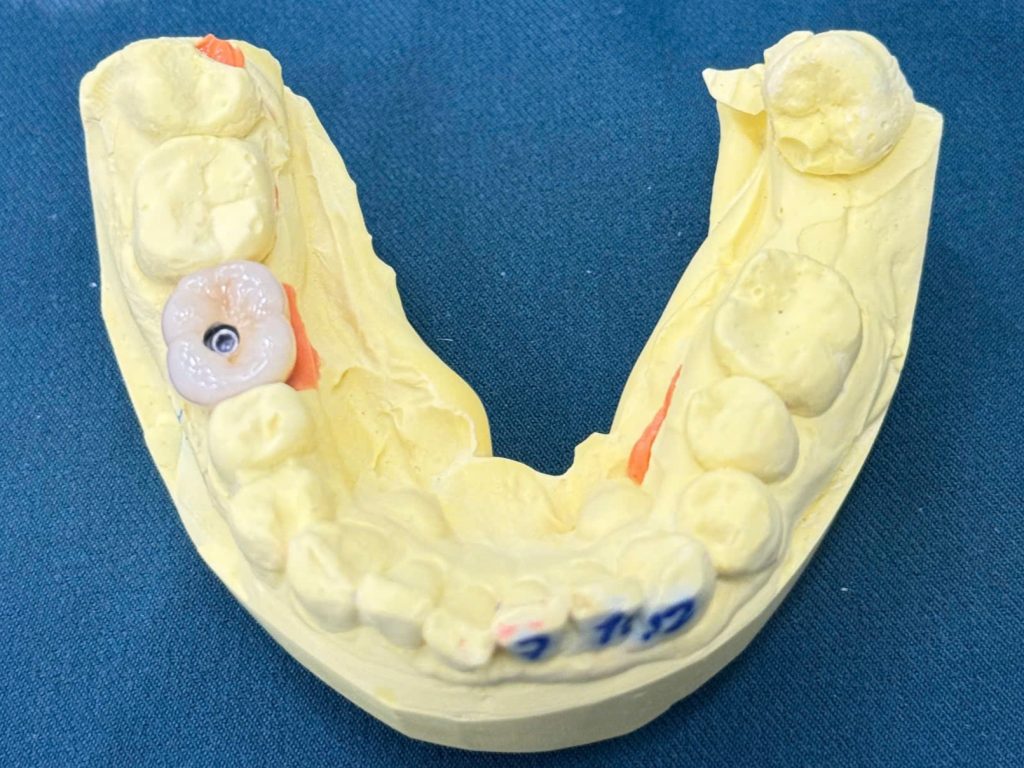

Bước 5 – Lấy Dấu & Chế Tác Răng Sứ